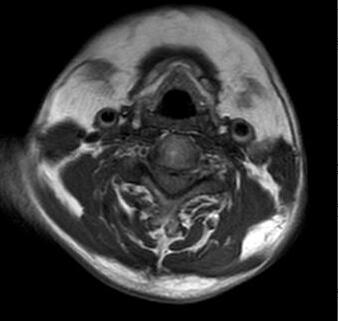

马德龙病的影像表现为颈项部等处脂肪组织蓄积增厚,可累及皮下或肌肉间隙,脂肪蓄积处没有包膜形成,蓄积脂肪内可有线状或网状纤维间隔,病变常常左右对称,颈部肌肉可受压、变细,蓄积脂肪组织内可有钙化或骨化。

李某颈部MRI